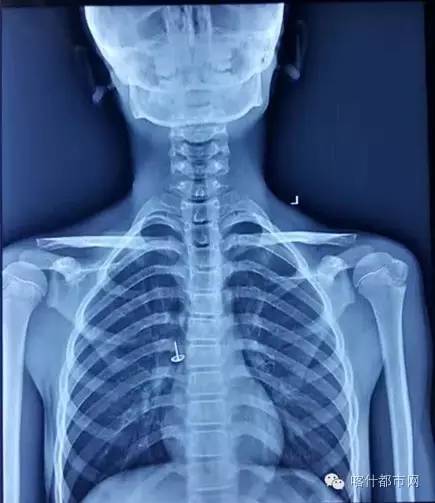

接到孩子后,立刻开展抢救工作,唐继鸣医生先进行术前会诊,发现孩子体内的东西惊呆了,因为他的支气管插着一颗图钉!

(孩子误吞这颗图钉将近一个月,因为害怕不敢告诉家人,发现的时候已经病变,情况十分危急!)

(从孩子支气管里取出来的图钉)